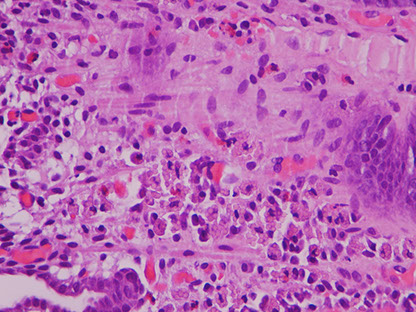

Figure 1: Gastric mucosal biopsies from children with autoimmune enteropathy often showed features of (a) chronic gastritis with increased lamina propria lymphoplasmacytic inflammation forming a superficial band within the mucous neck region. (b) In some cases, prominent intraepithelial lymphocytosis was identified within the surface, foveolar epithelium consistent with lymphocytic gastritis. (c) Concurrent autoimmune-related disorders were a common finding in patients with autoimmune enteropathy. Gastric biopsies taken from the fundus of case 14 demonstrated the features of autoimmune atrophic gastritis with partial parietal cell loss and superficial intestinal metaplasia. (d) In a subset of patients, multiple apoptotic bodies (arrows) were identified within the deep glandular mucosa.